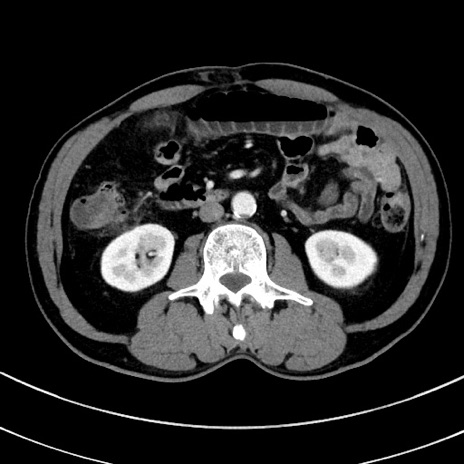

冠状断像

【症例】 60歳代男性

【主訴】 黒色吐物

【現病歴】 4日前から嘔気自覚、2日前の朝食後にも嘔気あり、自分で手で嘔吐反射起こし嘔吐したところ血が混ざっていたため受診。

【既往歴】 5年前汎発性腹膜炎を伴う急性虫垂炎で手術、高血圧、前立腺肥大症、高脂血症

【身体所見】 腹部正中に手術癩痕あり 腹部平坦・軟圧痛なし膨満感あり

【データ】WBC 8400、CRP 4.54